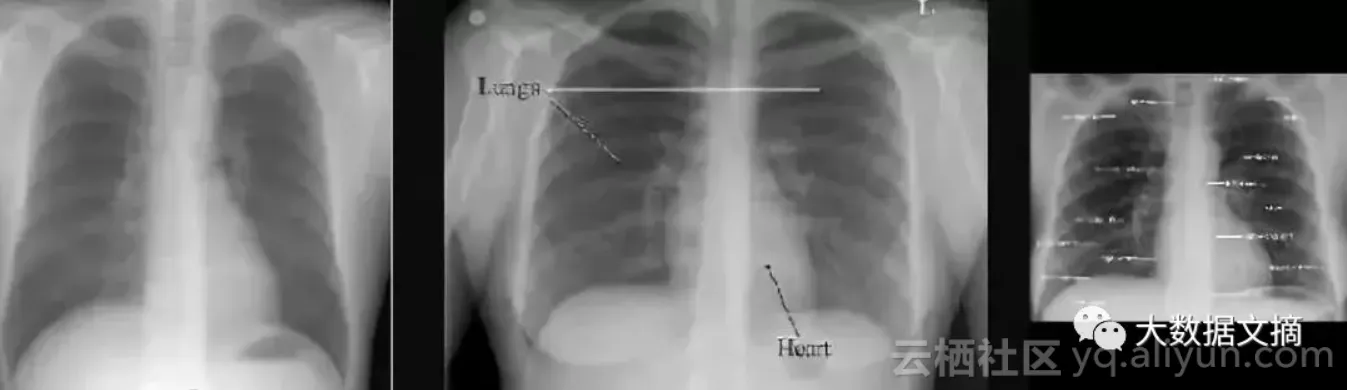

案例的主角是胸部X光图像。

由于设备制造商的不同,胸部X光的图像有可能是水平的,也可能是垂直翻转的。他们可能会倒置像素值,也可能会旋转。问题在于,当你处理一个庞大的数据集(比如说50到100万张图像)的时候,如何在没有医生查看的情况下发现畸变?

上面三幅图中,只有中间的图像存在“黑色边框在两侧”的情况,因而上面这一方案并不实用。

在旋转和竖直胸部X射线之间的差异真的是令人尴尬的简单。

答案是:不难!在视觉上,异常图片与正常图片完全不同。你可以使用一个简单的可视规则,比如说“肩膀应该高于心脏”,然后你就会得到所有正确的结果。鉴于解剖学非常稳定,所有人都有肩膀和心脏,这应该是卷积网络的可以学习的规则。